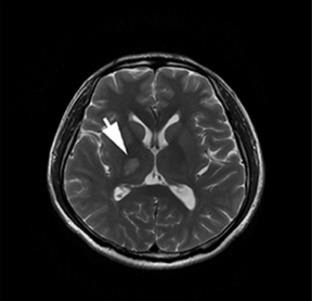

Photo retrieved from Frontiers in Neurology

- Inflammation of nervous system - causes headache, fever, disorientation, poor balance and stroke.